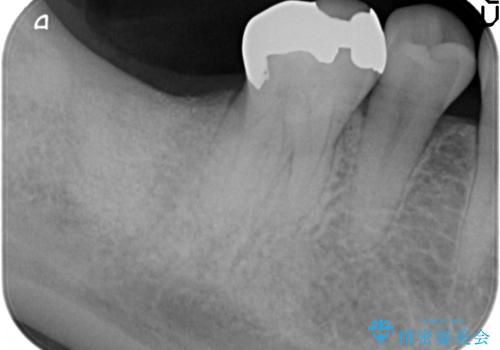

歯を失い、将来的にインプラントを埋入し咬合機能を回復していく場合、十分な骨量の確保は重要です。

今回抜歯後、骨が十分に確保できないとの判断から抜歯と同時に骨補填剤の填入を行いました。